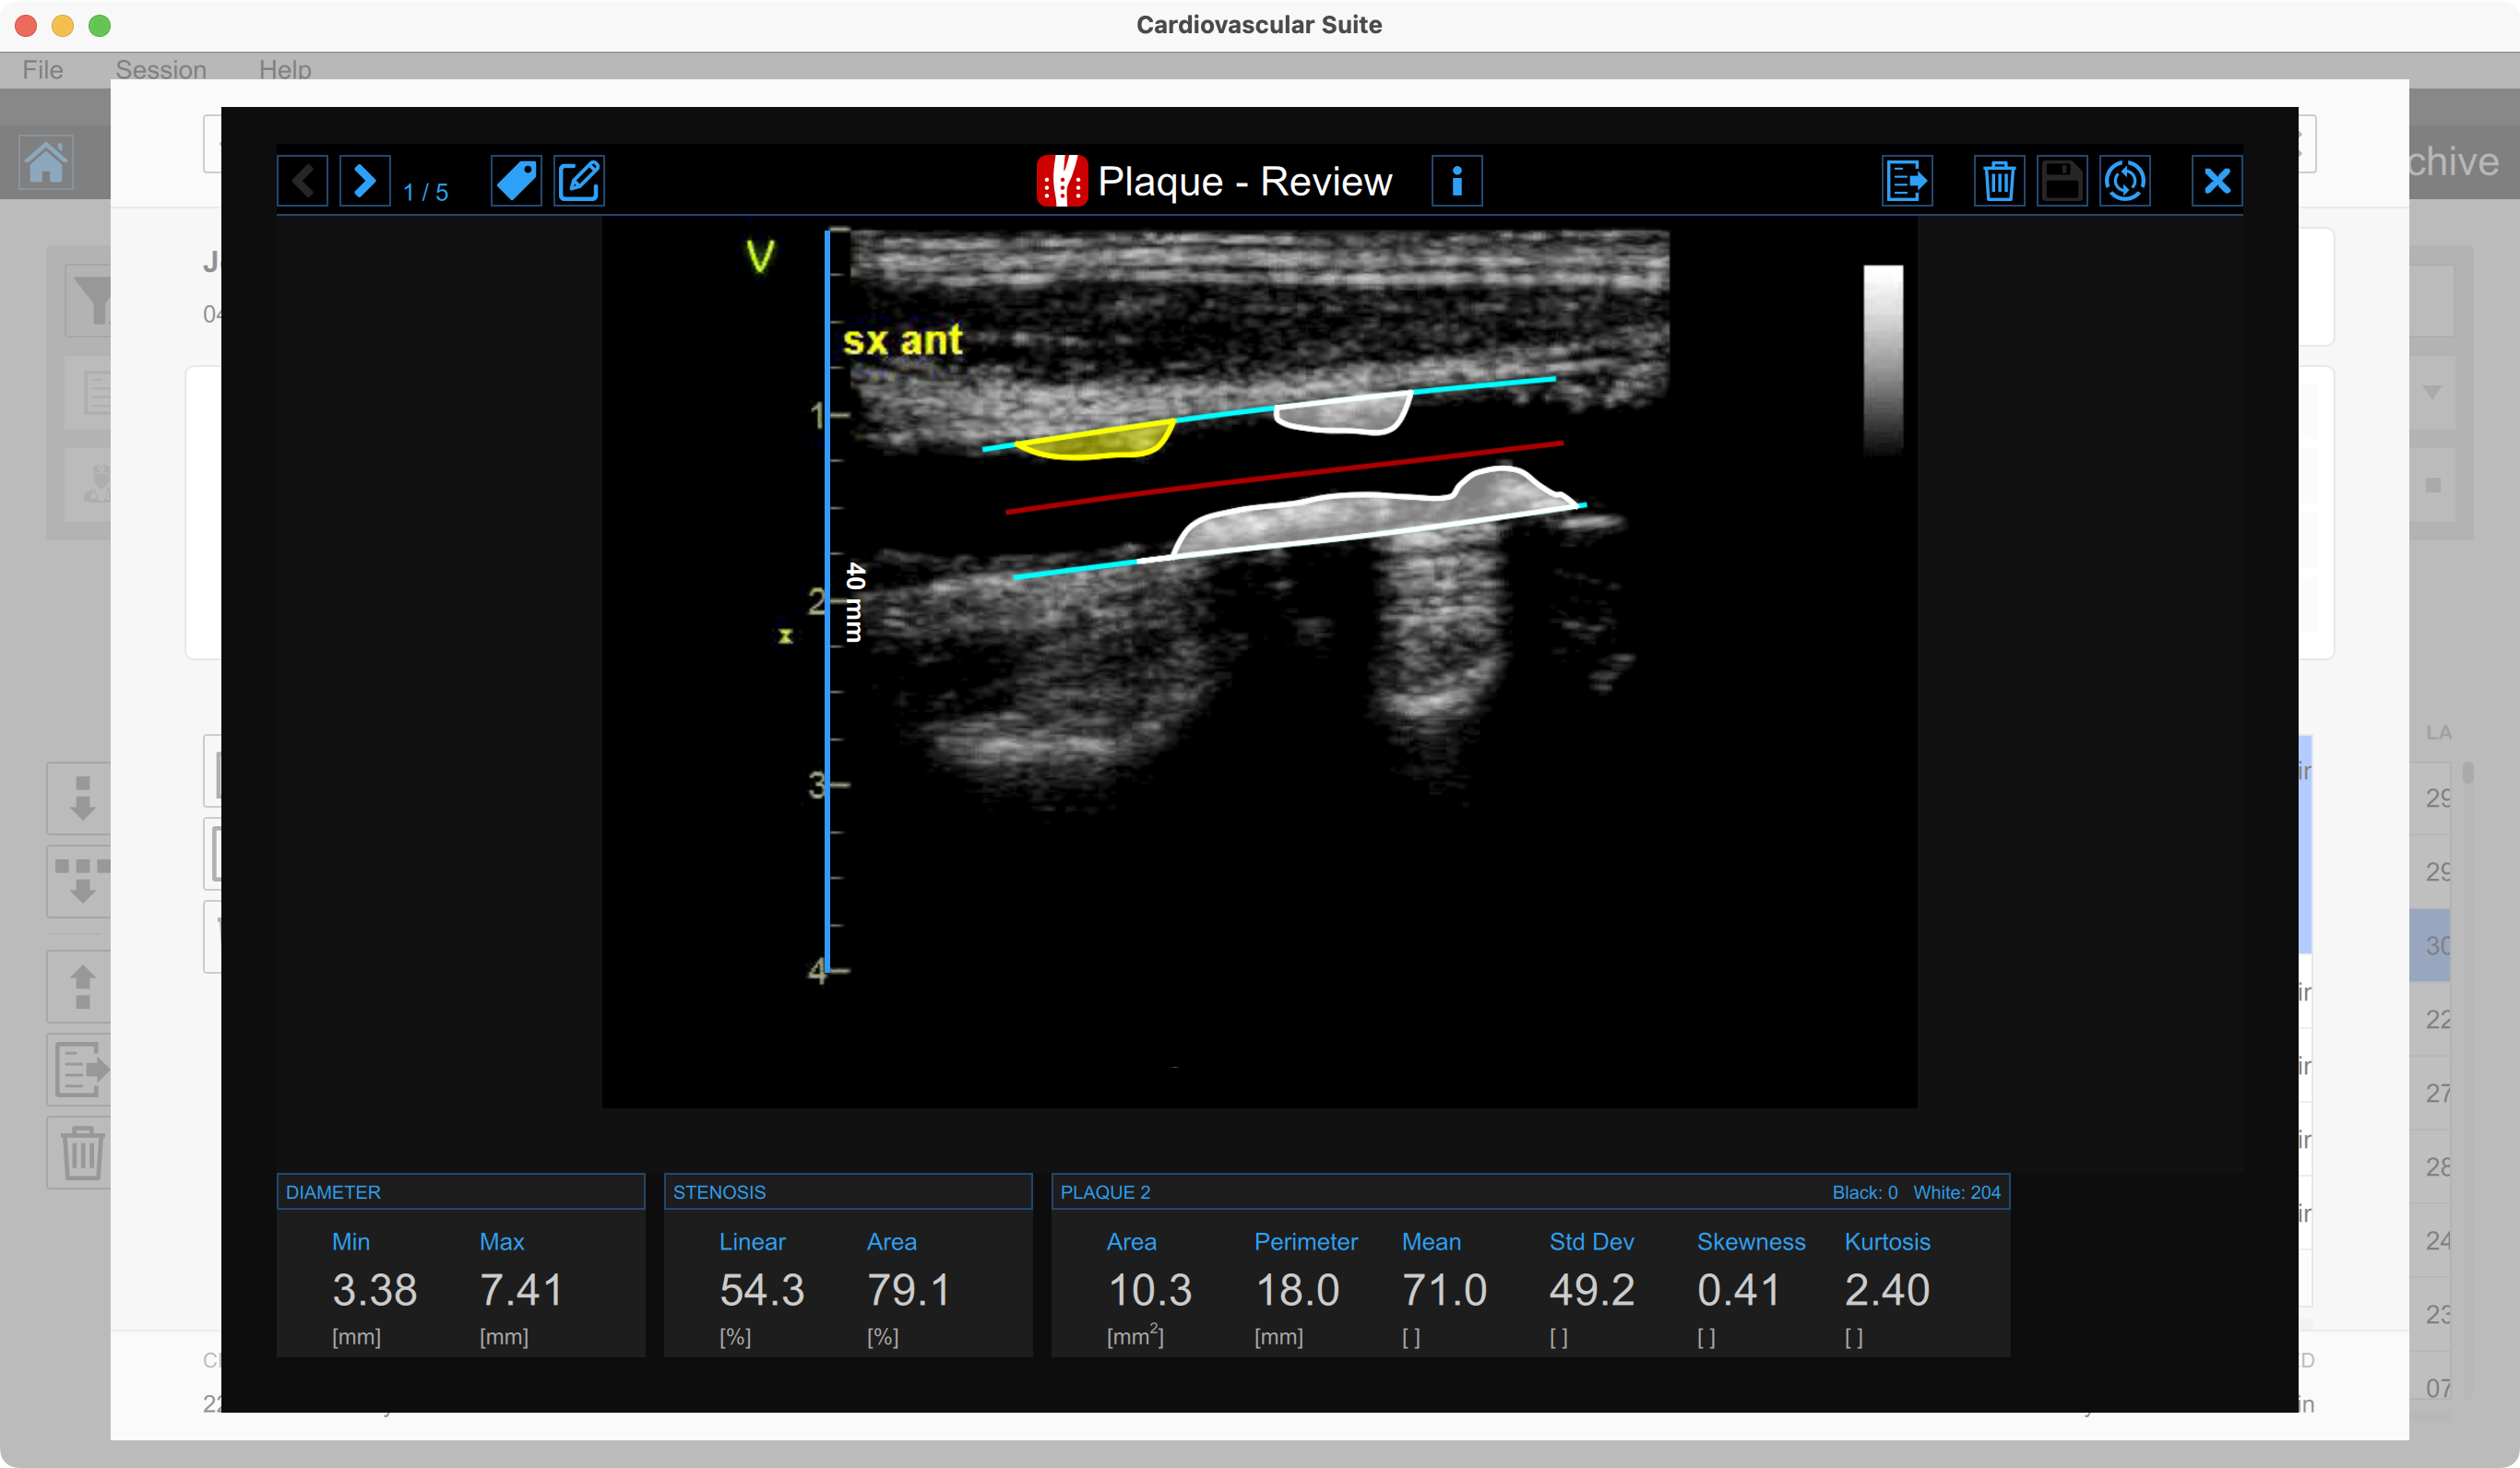

La fenêtre d'analyse affiche le résultat de l'analyse.

En bas de la page, les résultats suivants s'affichent :

• Diamètre min. [mm] : valeur minimale du diamètre.

• Diamètre max. [mm] : valeur maximale du diamètre.

• Sténose linéaire [%] : pourcentage de sténose linéaire (calculé sur le diamètre).

• Sténose surfacique [%] : pourcentage de sténose surfacique (calculé sur la surface de la section transversale).

• Surface de la plaque [mm²] : surface de la plaque sélectionnée

• Périmètre de la plaque [mm] : périmètre de la plaque sélectionnée.

• Moyenne de la plaque [] : valeur moyenne des niveaux de gris de la plaque sélectionnée.

• Écart type de la plaque [] : écart type des niveaux de gris de la plaque sélectionnée.

• Asymétrie de la plaque [] : asymétrie des niveaux de gris de la plaque sélectionnée.

• Aplatissement de la plaque [] : aplatissement des niveaux de gris de la plaque sélectionnée.